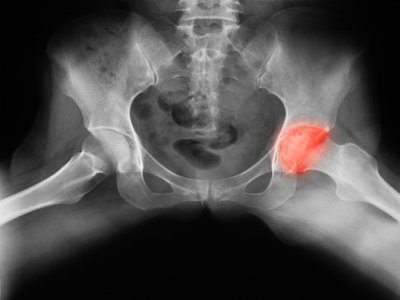

What Are The Symptoms Of Bone Cancer In Your Hip - What Are the Symptoms of Bone Cancer in the Hip ... / Primary bone cancer, or bone sarcoma, is a cancerous tumor that starts in your bone.. Once colon cancer reaches your bones, you can't be cured of the cancer. It may be worse at night or when the bone is used, for instance, leg pain when walking. 12 warning signs of bone cancer you should not ignore. Cancer in bone can cause intermittent or progressively severe localized bone pain where the cancer is in the bone. A sudden, noticeable new pain is the most common symptom of cancer that has spread to the bone.

Common symptoms of hip cancer symptoms of hip cancer may include: Signs and symptoms of bone cancer. Pancreatic cancer in the body or tail can also take longer to present with symptoms, allowing the tumor more time to grow or metastasize before it's found. While bone pain is the main symptom of bone cancer, and pain in the hip bone can be an indication of a tumor in the hip, there are often more likely other explanations for hip pain. Cancer of the hip bone may also cause fatigue and general lack of energy.

Cancer's Guide: The Best Natural Cures for Bone Cancer from 1.bp.blogspot.com Once colon cancer reaches your bones, you can't be cured of the cancer. Specific cancer location (leg, hip, arm, etc.). At first, it may subside with movement, but later, activity can make the pain worse, especially as the bone weakens. A high temperature (fever) of 38c (100.4f) or above If you are concerned about any changes you experience, please talk with your doctor. 12 warning signs of bone cancer you should not ignore. Pancreatic cancer in the body or tail can also take longer to present with symptoms, allowing the tumor more time to grow or metastasize before it's found. Symptoms of hip cancer include pain, fractures, and swelling or a mass in the hip.

Bone Cancer Symptoms Hip - Cancer News Update from popcultureworldnews.com It can come and go and be worse at night, gradually worsening and becoming continuous. Although breast cancer can spread to any bone, the most common sites are the ribs, spine, pelvis, and long bones in the arms and legs. The national cancer institute explains that pain and swelling in the hip are common symptoms of bone cancer. Bone metastasis can occur in any bone but more commonly occurs in the spine, pelvis. Bone cancer destroys normal bone tissue. Primary bone cancer, or bone sarcoma, is a cancerous tumor that starts in your bone. Hip bone cancer can also cause more general symptoms, including fevers and nights sweats, which are periods of intense sweating that occur during sleeping hours. If you are concerned about any changes you experience, please talk with your doctor.

Cancer in bone can cause intermittent or progressively severe localized bone pain where the cancer is in the bone. Bone cancer can begin in any bone in the body, but it most commonly affects the pelvis or the long bones in the arms and legs. Hip pain is a common complaint like that of knee or back pain. Other symptoms tend to be nonspecific or related to the primary type of cancer. Signs and symptoms of bone cancer.

Hip Bone Cancer Symptoms | LIVESTRONG.COM from img.aws.livestrongcdn.com The most common symptom of bone cancer is pain in the bones and joints, which may be worse at night or during activity. If you are concerned about any changes you experience, please talk with your doctor. Bone metastasis occurs when cancer cells spread from their original site to a bone. Pain is the most common symptom of hip cancer. Hip pain is a rare indicator of bone cancer, but take note of any swelling or severe ache that makes it hard to move symptoms of bone cancer in the shoulder: Cancer of the hip bone may also cause fatigue and general lack of energy. Pain in the affected bone is the most common sign of bone cancer. Rarely, people with a bone sarcoma may have symptoms such as fever, generally feeling unwell, weight loss, and anemia, which is a low level of red blood cells.

As the bone weakens, fractures can occur, though this is not common. This type of pain is usually characterized as burning, itching, or radiating. Bone cancer destroys normal bone tissue. Bone cancer is rare, making up less than 1 percent of all cancers. Pancreatic cancer in the body or tail can also take longer to present with symptoms, allowing the tumor more time to grow or metastasize before it's found. While bone pain is the main symptom of bone cancer, and pain in the hip bone can be an indication of a tumor in the hip, there are often more likely other explanations for hip pain. Your red blood cell levels may drop, causing anemia. Less common symptoms can include: Pain is the most common sign of bone cancer, and may become more noticeable as the tumor grows. Bone pain can cause a dull or deep ache in a bone or bone region (e.g., back, pelvis, legs, ribs, arms). Hip bone cancer can also cause more general symptoms, including fevers and nights sweats, which are periods of intense sweating that occur during sleeping hours. As shoulders are one of the most common sites of chondrosarcoma, it is important to know your body and distinguish usual muscle strain from the. Cancer in bone can cause intermittent or progressively severe localized bone pain where the cancer is in the bone.